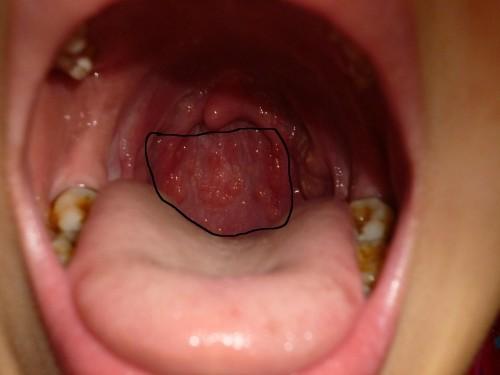

喉咙有泡泡,喉咙长泡泡

喉咙长泡泡

喉咙有泡泡图片

喉咙长泡泡图片

小孩喉咙有泡泡图片

喉咙里面长泡泡图片

喉咙起泡图片

舌根喉咙处起泡泡图片

喉咙内壁长了很多泡

喉咙内壁长泡图片

喉咙壁上长了好多泡

慢性咽炎喉咙滤泡图片

小孩喉咙长泡的图片